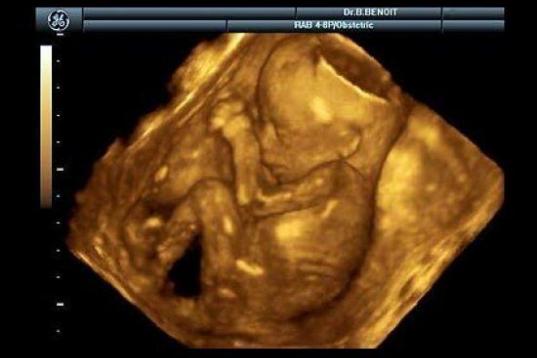

En esta galería puedes ver en fotos como es el desarrollo de un feto de semana en semana:

Desarrollo del feto, en fotos

Ver la galería